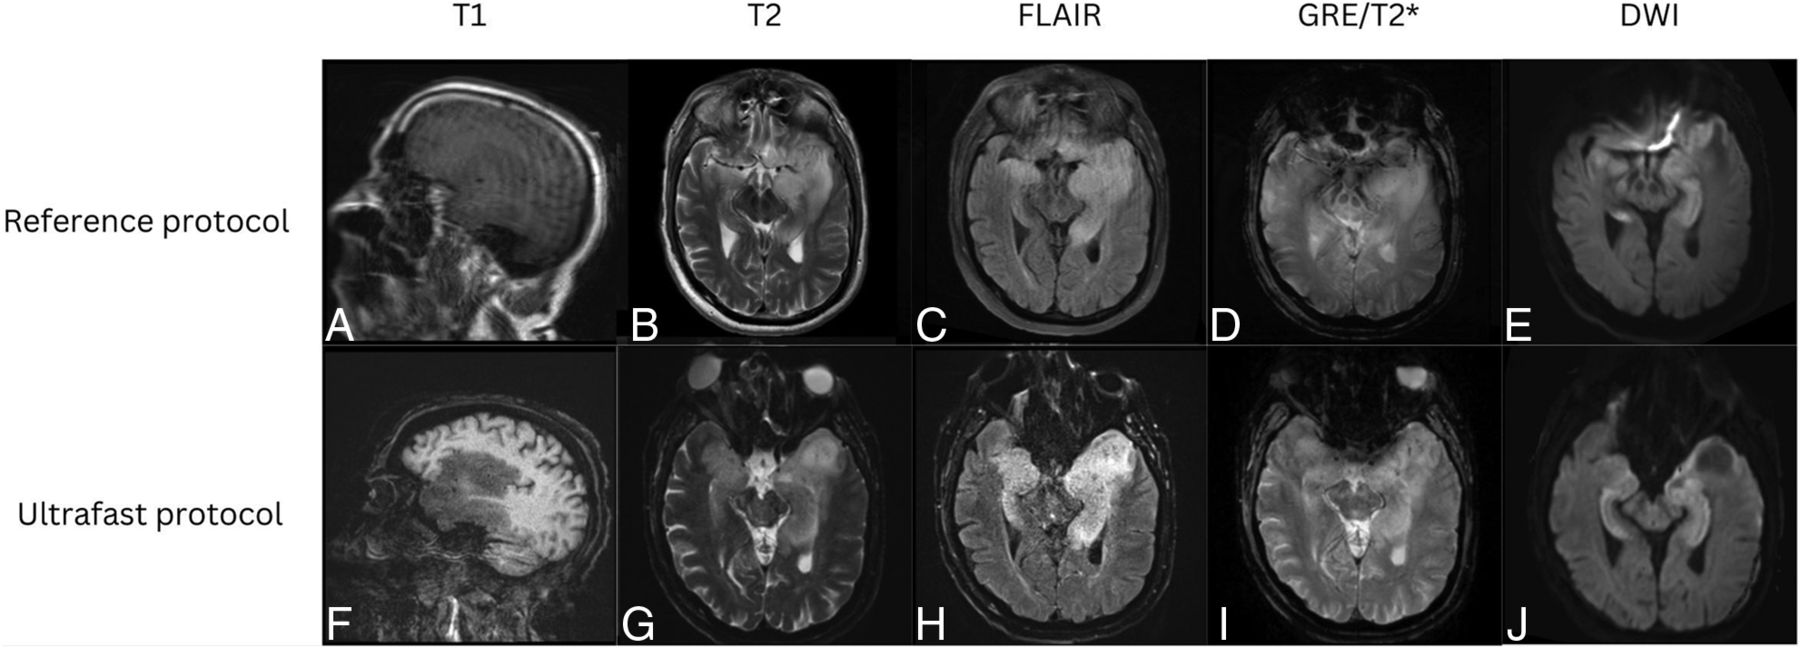

Representative images from 4 clinical cases are shown in Figures 3⇓⇓–6, demonstrating similar diagnostic quality between the ultrafast brain MR protocol images and the reference brain MR protocol images. Figure 3 shows a case of amyloid angiopathy with scattered foci of microhemorrhages. There is blurring of the findings on the reference GRE sequence due to motion artifact, and the foci of susceptibility signal are better appreciated on the ultrafast T2* images. Figure 4 shows a case of herpes simplex virus encephalitis with T2/FLAIR hyperintensity and restricted diffusion in the left greater than right mesial temporal lobes, visualized equally well on both the reference and the ultrafast brain MR protocols. Figure 5 shows a case of punctate subacute infarct in the left centrum semiovale on a background of chronic small vessel ischemic disease, visualized equally well on both the reference and the ultrafast brain MR protocols. Figure 6 shows a case of glioma involving the left thalamus with both the reference and the ultrafast brain MR protocol demonstrating ill-defined T2/FLAIR hyperintensity centered in the left thalamus.

Patient with a diagnosis of amyloid angiopathy. Reference sagittal T1-weighted (A), axial T2-weighted (B), FLAIR (C), SWI (D), and DWI (E) show scattered foci of susceptibility signal in the left greater than right frontal lobes consistent with chronic microhemorrhages. The findings were more conspicuous on the ultrafast sagittal T1-weighted (F), axial T2-weighted (G), FLAIR (H), SWI (I), and DWI (J) because of motion artifact on the reference MR images.